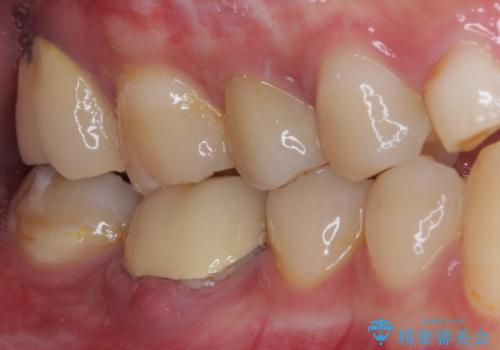

病変が消退しているかどうか、半年、1年とレントゲン写真で経過観察を行う必要があります。

海外に行かれていた都合で、術後2年での経過観察となりましたが、無事に病変の消失が認められました。